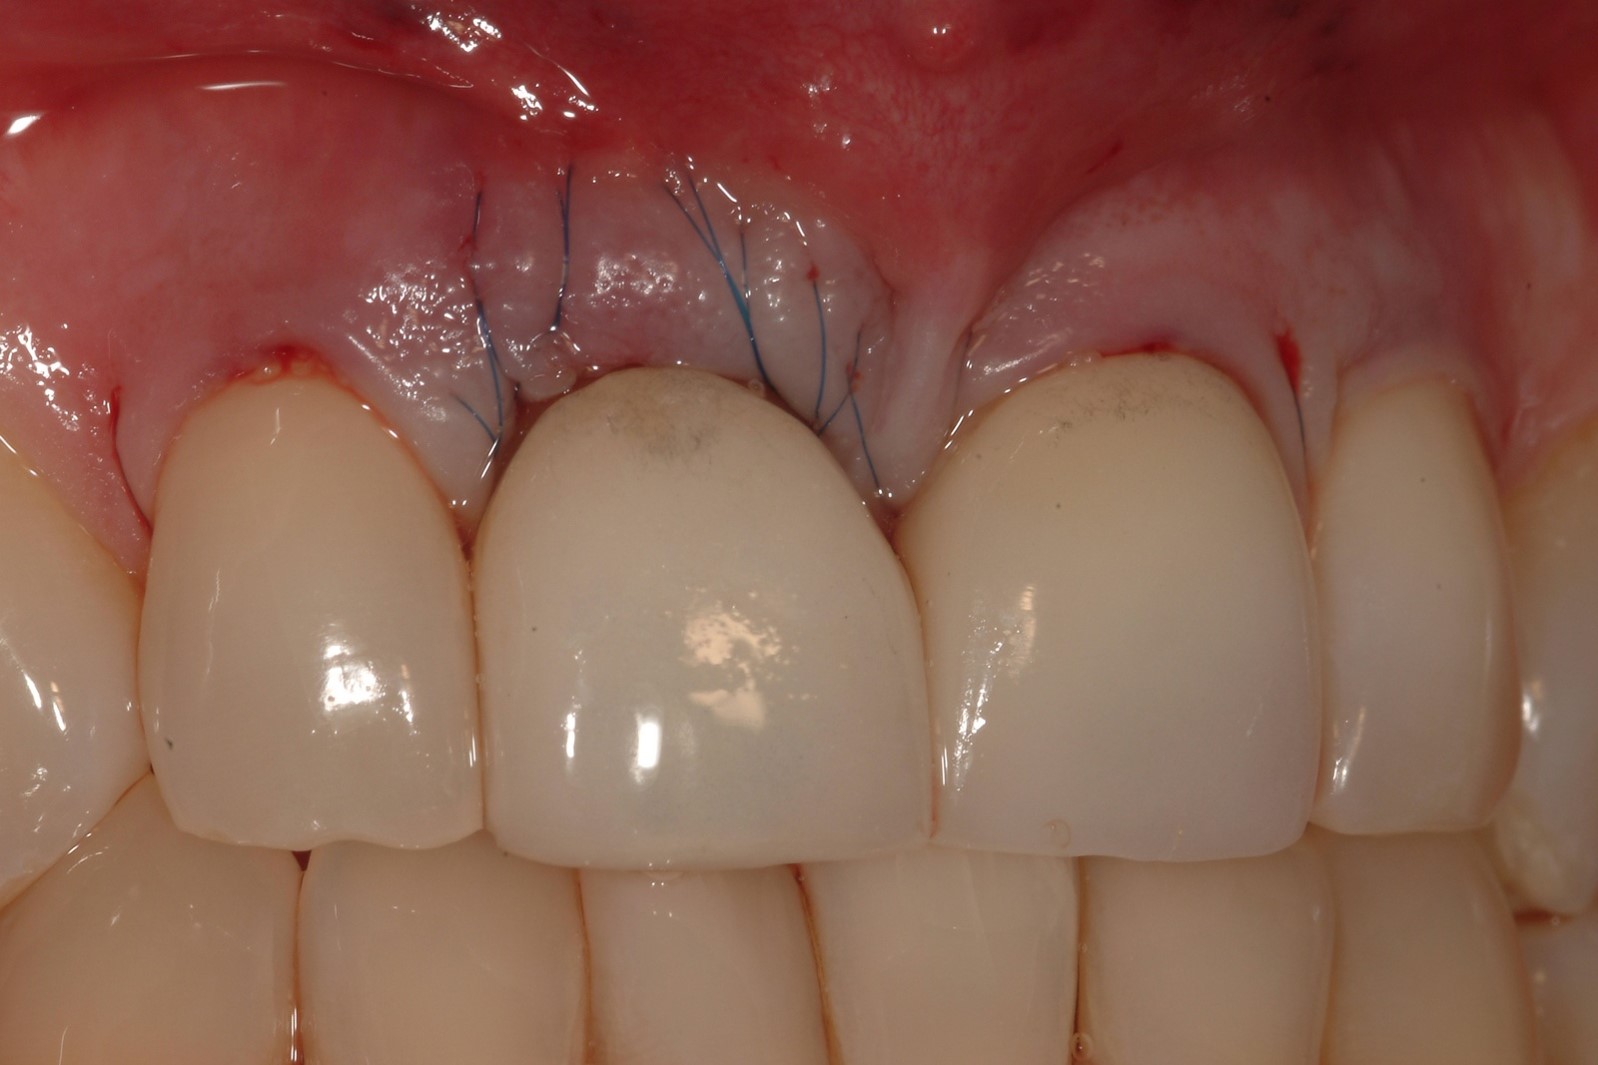

Fig 16. Close-up view of the patient’s gingival architecture following tissue graft healing.

Figure 16

However, by giving consideration to the most appropriate and minimally invasive sequence of care, this led to performing predictable procedures beginning with a tunneling procedure with a small connective tissue graft (Figure 15). Once the connective tissue graft healed (Figure 16), extra soft tissue with a thickened biotype was available. This would enable minimally invasive extraction using piezosurgery—without damaging the soft tissues (Figure 17)—followed by immediate implant placement according to 3D implant treatment planning (Figure 18 through Figure 20).

After implant placement, bone graft material enhanced with growth factor was also placed, which would be protected by the extra tissue height (Figure 21 and 22). An Essex appliance was used for the first 2 weeks (Figure 23), and once the soft tissues healed, the crown on the adjacent tooth could be removed to allow for an interim cantilever prosthesis.